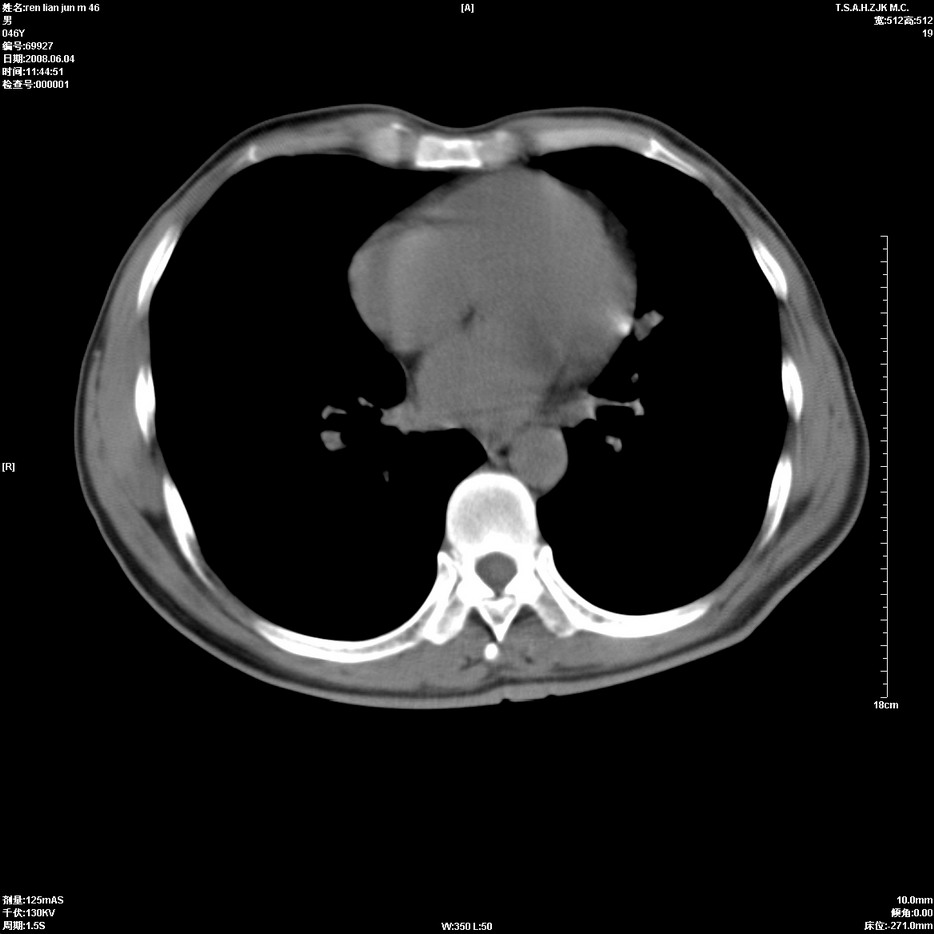

以下是引用qiu999在2008-6-5 17:14:00的发言:[br]考虑右肺中心型肺癌.颅内应做增强检查.

以下是引用形影不离在2008-6-5 19:18:00的发言:[br]右肺中心型肺癌并纵隔及左侧腋窝淋巴结转移,颅内应做增强检查。

以下是引用杀毒软件在2008-6-5 18:33:00的发言:[br]支持考虑右肺中心型肺癌,颅内病变是不是转移,不好说